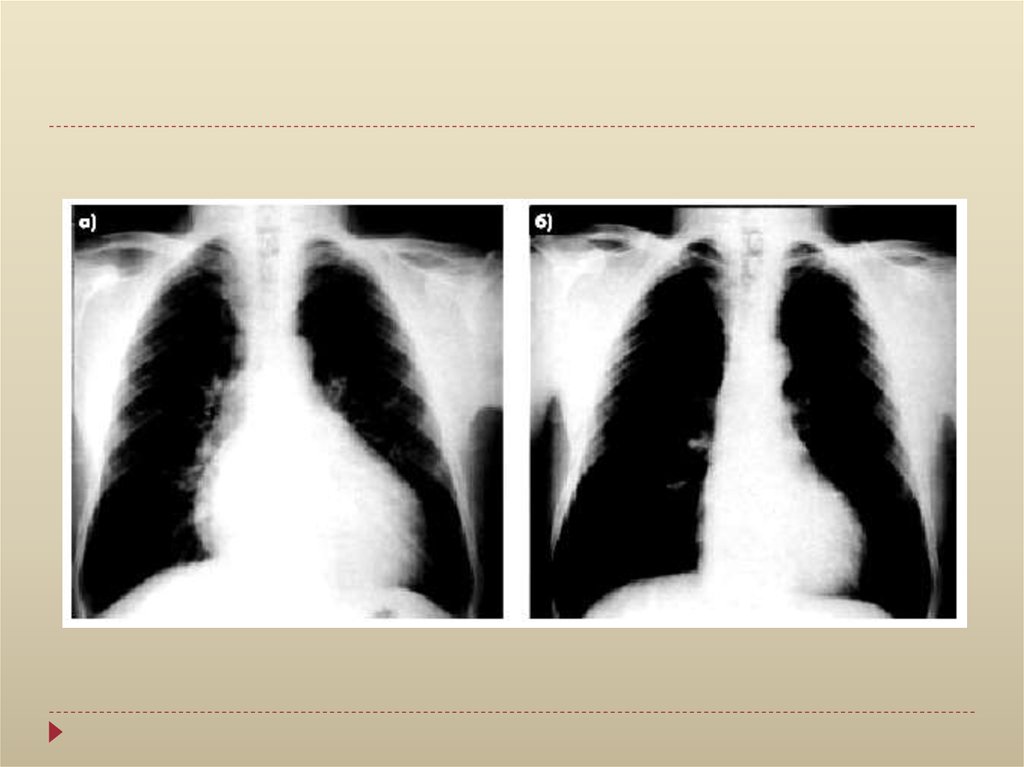

Рентгенологическое исследование:

увеличение тени сердца

сглаживание сердечного контура,

исчезновение “талии” сердца

ослабление пульсации контура тени сердца

треугольная форма тени сердца